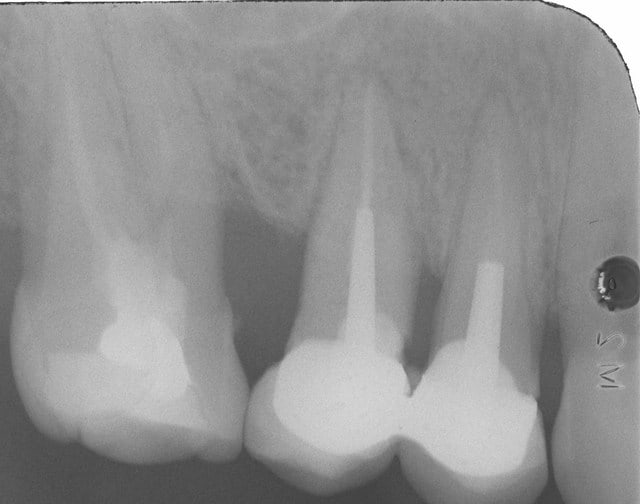

regarde sur la molaire , j'ai différé l empreinte de 7 jours.

la photo est le jour de l'empreinte , or le jour de la taille j'etais juxta voire infra .

si j'avais pris l'empreinte le meme jour je l'aurais eu gros...

ci joint la photo de la molaire d'en haut le jour du scellement.

ha la voilà

16 i9zdkt - Eugenol